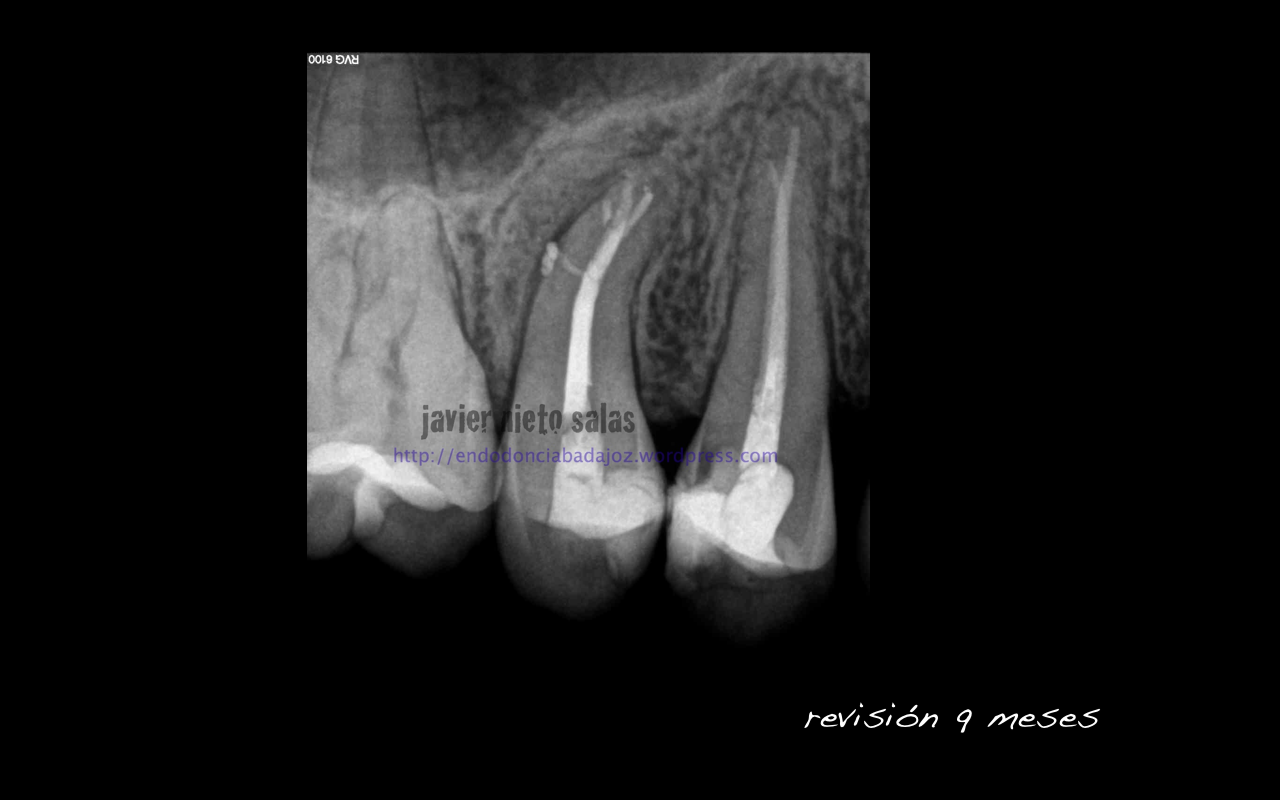

Después de unos 9 meses, la paciente nos llegó a revisión, la lesión ha regenerado correctamente, éxito en el tratamiento: